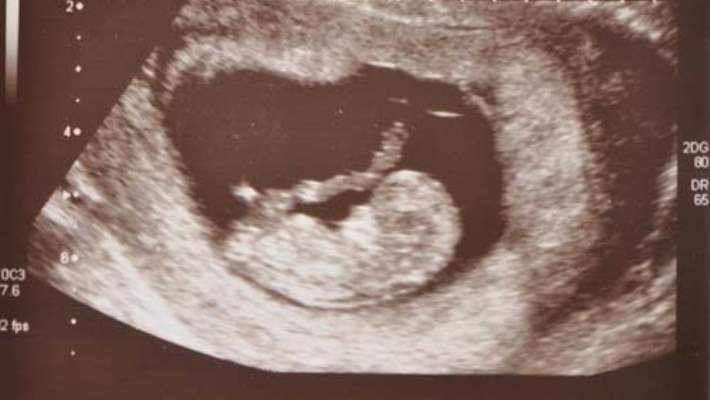

Hamileliğin 9. Haftasında Bebeğin Organlarının Durumu Nedir?